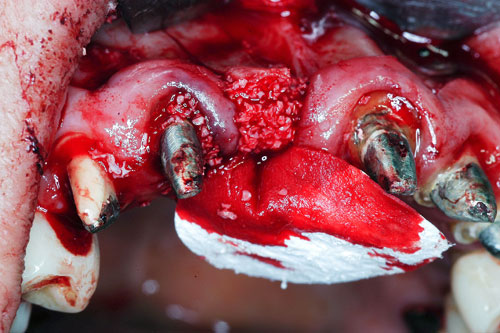

Mientras dichos movimientos ortopédicos se producen (período que supondrá otros seis meses), estudiamos los actos quirúrgicos a realizar en los cuatro implantes que pondremos. De acuerdo al estudio Desatascan realizado observamos tres situaciones diferentes: 1º-El Primer Molar Inferior Izquierdo, lo instalamos mediante Cirugía Minimamente Invasiva , con la aplicación de una Férula Quirúrgica Obtenida de los datos del scanner tratados con un programa de CMI (Cirugía Minimamente Invasiva), previa prueba en un modelo estereolitográfico, ya que la altura ósea era apenas de 9 mm. 2º- El Primer Molar Superior Derecho, se implantará mediante una ligera Elevación Atraumática (Trans alveolar) de Seno una vez logrado el espacio mesio distal necesario. 3º- El Incisivo Central Superior Derecho ausente, cuenta con un sustrato óseo prácticamente inexistente. El espesor de la tabla era de menos de 2 mm. Los caminos posibles a seguir para contar con una Rehabilitación de piezas independientes son dos: Optamos por esta segunda opción por ser menos cruenta y no necesitar de una zona dadora. Técnica esta que pondremos en práctica en dos etapas diferidas: 1º-Incisión horizontal palatinizada, incisiones peri rodetes gingivales e incisiones de descarga. Dilatación que comenzamos con dos incisiones de descarga sobre la cortical vestibular realizadas con disco. y el comienzo de la dilatación propiamente dicha mediante una hoja de bisturí, para luego seguir con un periostótomo . Recién después de alcanzada una cierta separación de la cortical vestibular de la palatina, empezamos con los dilatadores roscados. En este punto podríamos haber utilizado sin riesgos un Implante de 3,8 mm de diámetro, pero a fin de mejorar la estética del pilar emergente decidimos rellenar con material osteoconductor y osteoinductor (BiOss) y cubrir mediante membrana reabsorvible ( Bio Guide). 2º-Implantación seis meses después. Mientras se van cumpliendo los tiempos antes mencionados, y comprobamos reiteradamente la funcionalidad de la oclusión con los provisorios, tomamos impresiones definitivas y construimos primero el maxilar inferior, para definir en primer término la porción inferior de la Guía Anterior., y a nivel posterior Curvas y Microplanos. Para luego realizar los cuadrantes premolar- molar del superior: La espera de la regeneración ósea y sus tiempos pertinentes, más la espera de los tiempos de la implantación, nos obligaron a modificar las etapas del protocolo D.AT.O de manera de mantener la –D- mediante el sector superior de la GA. en provisorios, mientras fuimos resolviendo en forma definitiva los demás sectores. Ya pasados los meses necesarios para recrear un hueso adecuado en el área del Incisivo Superior Derecho, procedemos a resolver la implantación de dicha zona, observando que todo el esfuerzo dedicado al mismo había sido inútil, ya que la formación de hueso se produjo minimamente. Cuatro meses después tomamos impresiones del sector Antero Superior de la Guía Anterior, incluyendo el arrastre de un transfer . Seguimos modelando la encía con un nuevo juego de provisorios. Y se construye entonces el sector superior de la Guía Anterior. Se efectúa un control radiográfico a los 6 meses. Se ha intentado mostrar en esta Rehabilitación, que a pesar de las distintas circunstancias de cada paciente, siempre debemos tener en cuenta la necesidad de ejercer la DESOCLUSIÓN del caso como prioridad número uno, para luego perseguir la ALINEACIÓN TRIDIMENSIONAL de las arcadas y obtener así una OCLUSIÓN equilibrada. D.AT.O. ES EL PROTOCOLO QUE DEBEMOS SEGUIR EN TODA REHABILITACIÓN. BIBLIOGRAFÍA 1)William Mc Horris,B.S.,D.D.S. Oclusión. Con especial énfasis sobre :El rol funcional y parafuncional de los dientes anteriores. 2)Von Spee , Craff(Anatomista alemán, describió la curva de compensación de la articulación de molares y premolares).CURVA DE SPEE 1.89 3)Stuart,D.”Some aspects of the inervation teeth.”Procedings of Royal Society of Medicine.20:1675,19274)Muhleman,H. y Savdir,S”Tooth movility-its causes and significance”Journal of Periodontology ,36:153,Marzo ,Abril,1965. 4)Muhleman,H. Y Savdir,S”Toothmovility its causes and significance” Journal of Periodontology,36:153,marzo,abril,1965. 5-Oclusión y Diagnóstico en Rehabilitación Oral. 6-Anatomia Odontológica. 7-A contribution to the study of the movementes of the mandible. 8-Celenza F.W, Nadeskin J.F.,Oclusión.Situación actual. 9-D´Amico 10-Dawson P.E. 11-Huffman –Regenos. 12-Hobo S.-Takayama H.A. 13-Lucia V.O 14-Mc Horris. 15-Mc Horris. 16-Stuart C. 17-Vartan Veshnilian 18-Alvarez Cantoni H. AUTOR:Ratificación del Protocolo en Rehabilitación Bucal a pesar de las incidencias propias de cada caso clínico. A propósito de un caso.

Cubrimos con membrana reabsorvible.

A-Injerto Óseo en Bloque.

B-Dilatación Crestal mediante Dilatadores Roscados previa Corticotomía Vertical.

Esperamos seis meses antes de implantar.

No obstante pudimos implantar satisfactoriamente mediante un implante de 4.2 mm. de ancho y 14 mm. de largo, con una nueva R.O.G.